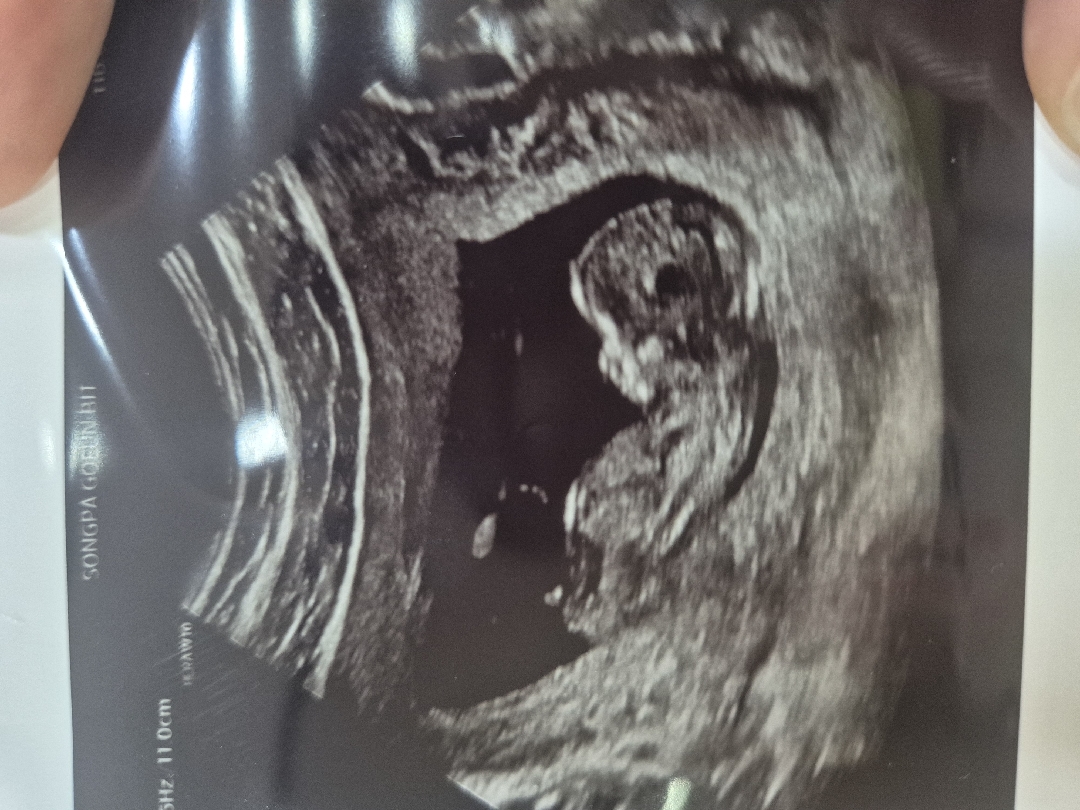

각도법 한번 봐주실분 ㅠㅠ

12주차 4일째입니다아 각도법 잘 보시는분 계실까요ㅠㅠ 넘 궁금하네용